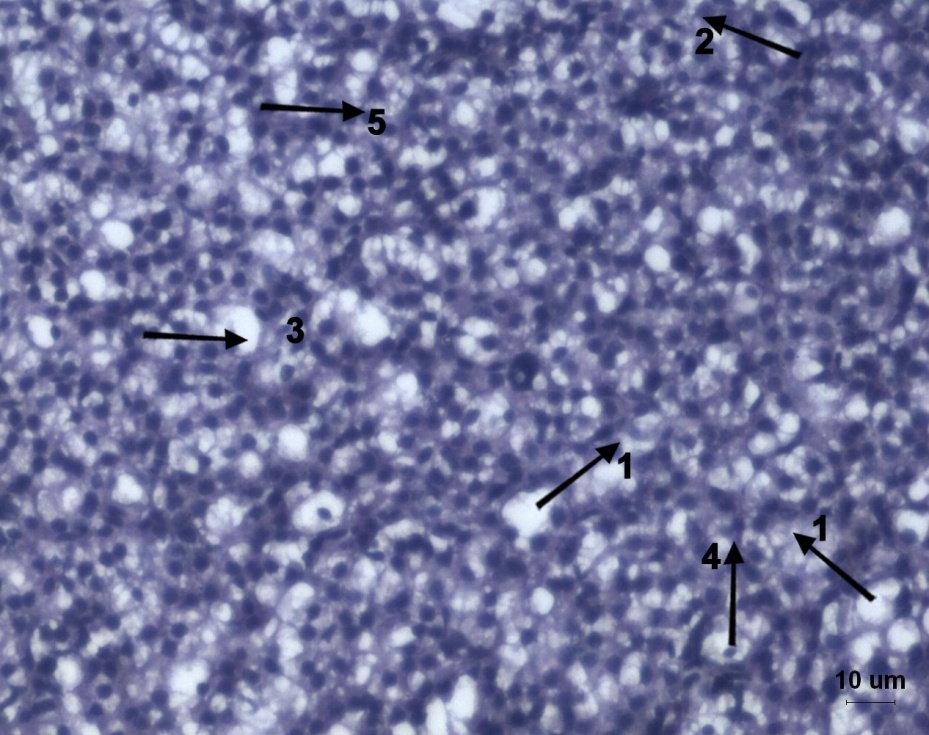

Fig. 6: Histological alterations of liver of Labeo rohita fish exposed to lead acetate and fed with normal fish food stained with Hematoxylin and Eosin showing 1-Vacuolization of nucleus, 2-Cytoplasmic degeneration in hepatocytes, 3-Congestion of blood vessels, 4-Leukocyte infiltration, 5-Hypertrophy of hepatocytes. Scale Bar = 10 µm

The control group liver tissue (fig. 2a) generally exhibited a normal architecture with polygonal-shaped hepatocytes. These hepatocytes are located among blood capillaries called sinusoids, forming cord like structures known as hepatic cell cords. The liver of lead acetate exposed fish fed with normal food (fig. 2b) showed clear large vacuoles found between hepatocytes, congestion of blood vessel, leukocytic infiltration, necrosis and degeneration of blood vessel hypertrophy. Congestion is a blood circulation disturbance due to increased volume of the blood in the blood capillary. Vacuolar degeneration is known as an acute swelling of the organ. In addition, loose arrangement of hepatic cells and hepatocytes with large intracellular and intercellular vacuoles were observed [34]. The histopathological lesions in the liver may be attributed to enzymatic changes or metabolic changes due to contaminated water. The histology of the fish fed with supplementary food (fig. 2c) showed apparently normal structure of liver.